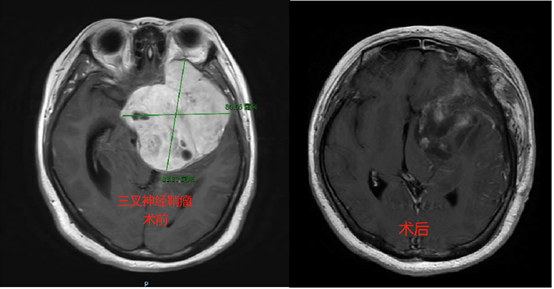

看看我们近期收治的几例良性肿瘤患者,您还敢不做颅脑的体检嘛?

7.闭经泌乳,不孕不育。育龄妇女非妊娠的闭经、泌乳常为垂体肿瘤的首发症状。男性主要表现为阳痿和阴毛、腋毛、胡须脱落、皮肤细腻等。出现上述症状不要只就诊于妇科或男科哟,说不准是大脑的事儿呢。

8.肥胖、肢端肥大、样貌变丑、不明原因的三高、睡眠呼吸暂停。这也可能是垂体瘤的首发症状。